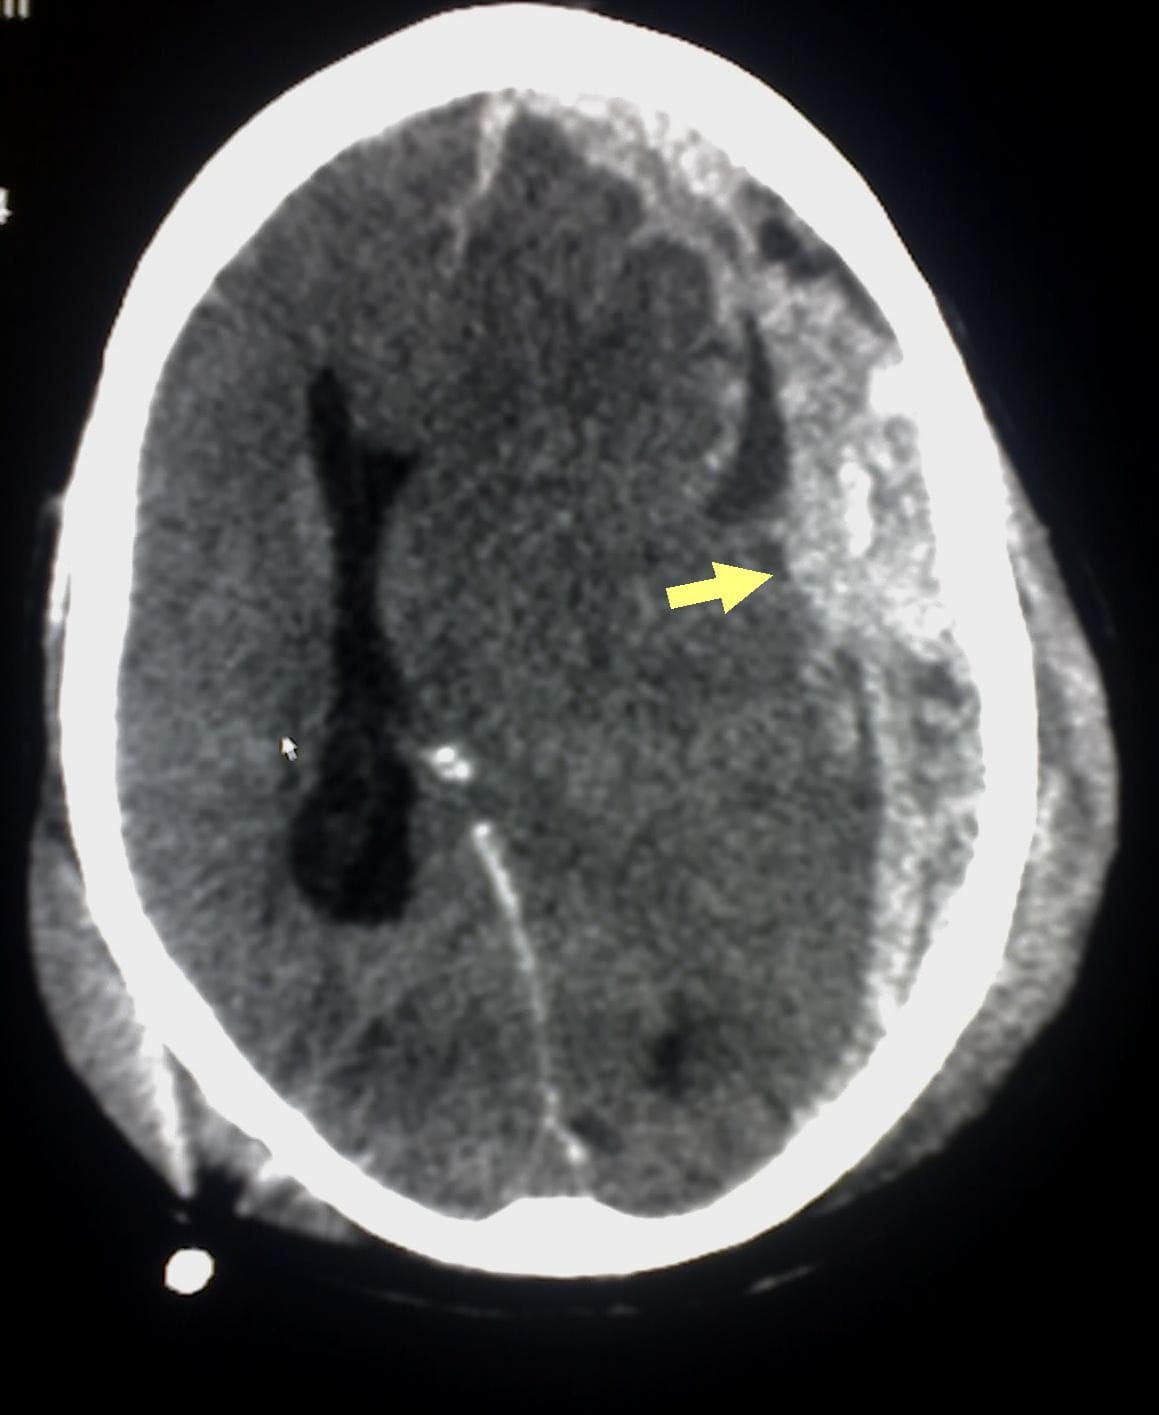

L'hématome sous-dural, ou hémorragie sous-durale, désigne l'épanchement de sang dans les espaces méningés. À la suite d'un traumatisme crânien avec lésion des petites veinules qui traversent l'espace sous-dural, l'hémorragie a lieu entre l'arachnoïde qui entoure le cerveau et le feuillet interne de la dure-mère qui est en contact avec la boîte crânienne. L'hématome ne peut pas traverser de l'autre côté du cerveau par rapport au côté d'origine de l'hémorragie. En effet, la faux du cerveau sépare en deux l'espace sous-dural. Les hématomes sous-duraux peuvent causer une augmentation de la pression intracrânienne, avec compression et lésion du cerveau. Le syndrome du bébé secoué est une cause fréquente de l'hématome sous-dural chez les enfants de moins de 6 mois. On attribuait généralement ce secouement à un parent ou un soignant qui, excédé par les pleurs de l'enfant et en désespoir de cause, le secoue pour le faire taire. Or en 2017, des statistiques affirment qu'un bébé secoué l'a été en moyenne 10 fois, ce qui invalide cette ancienne représentation des choses. 13 à 40 % des enfants ainsi secoués décèdent, et les survivants ont généralement des séquelles à vie. Elle est basée sur la vitesse à laquelle ils surviennent. On peut distinguer : l'hématome sous-dural aigu C'est une urgence médicale, avec une détérioration neurologique aiguë due à une augmentation de la pression intracrânienne. Le taux de mortalité est élevé si un drainage chirurgical n'est pas fait. Un syndrome d'hypertension intracrânienne. Les hémorragies aiguës se développent fréquemment après une subite accélération/décélération. Le pronostic est plus grave s'il y a une contusion cérébrale associée. Cependant, même si l'hématome sous-dural se développe rapidement, il est moins rapide que l'hématome épidural qui est dû à une rupture d'une ou plusieurs artères. Le taux de mortalité associé à l'hématome sous-dural aigu est compris entre 60 % et 80 %. l'hématome sous-dural chronique Il se développe lentement, le sang coagule et devient encapsulé dans du tissu fibrotique.